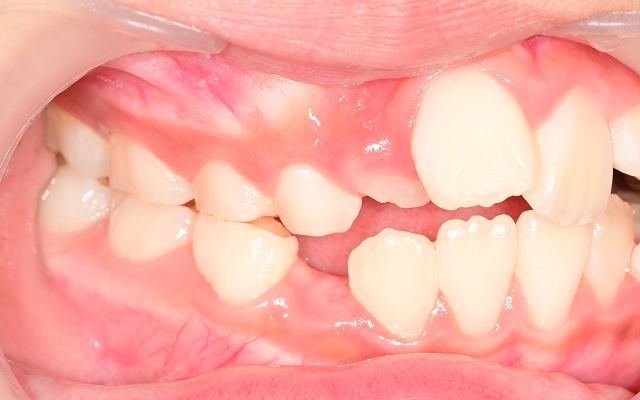

• 03

교합 불균형으로 턱관절 통증, 비대칭 얼굴선이 생길 수 있음